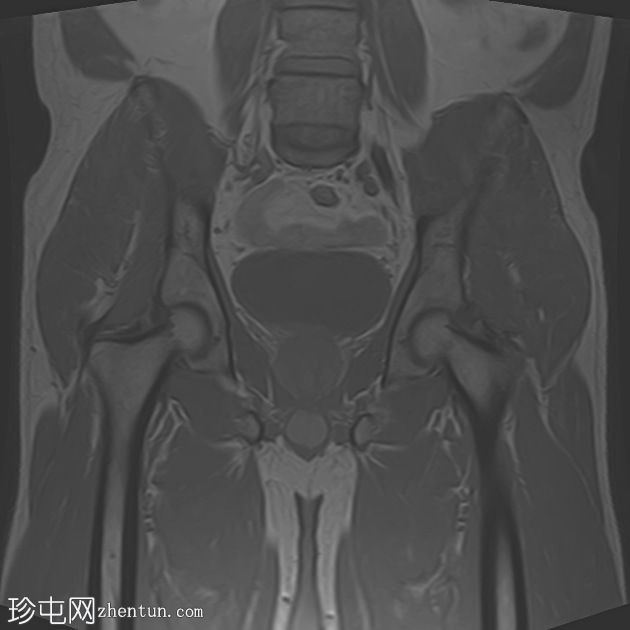

轴位

T2加权像

左侧股直肌近端至中段肌纤维内可见一长条状、边界清晰的肌内肿块,其大小约为:头尾径14.4 cm,横径6.6 cm,前后径2.7 cm。

该病灶在所有序列上均呈脂肪信号,T1加权像上呈高信号,脂肪抑制像上信号完全抑制(假性高信号)。

未见厚间隔、结节状结构或非脂肪成分。